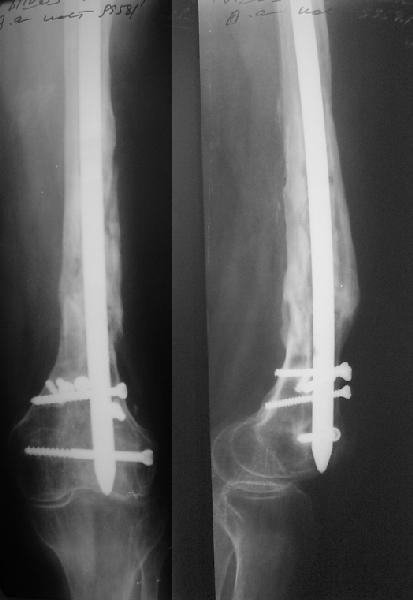

В 2002 г. была у нас больная с ложным суставом бедра и остеомиелитом (как оказалось), после удаления пластины. Гвоздь с блокированием.

Потекло через месяц - открылось 2 свища по старому рубцу от давно удаленной пластины. На фоне гноя раза три завинчивал обратно винты, которые вылезали латерально, прямо через свищ. Потом таки провел дополнительно винты мимо гвоздя, и убрал вверху статический винт. Острый гнойный процесс стих, свищи мыла она дома дважды в день водным хлоргексидином, ходила с возрастающей нагрузкой, а к 10 мес. и свищи закрылись, и срослось. Итоговые снимки от 18 апреля 2003 г. прилагаю.

Выполненный остосинтез нестабилен. Штифт надо заменить по "размеру" на солидный, дистльно три запирающих винта. Успехов!

Отправитель: Alexander Chelnokov 21 Январь 2005, 21:31

Перелом спиральный, то есть низкоэнергетический, так что со сращением дело обстоит уже неплохо, лишь бы "костоеда" не развилась. Отломки выглядят уже стабилизированными костной мозолью, так что довводить винты, наверно, уже незачем. Разве что при клинической оценке подвижность еще есть - тогда можно для стабилизации наложить простейший аппарат, не опасаясь контакта его элементов с гвоздем, поскольку места в дистальном метафизе оставлено более чем достаточно.